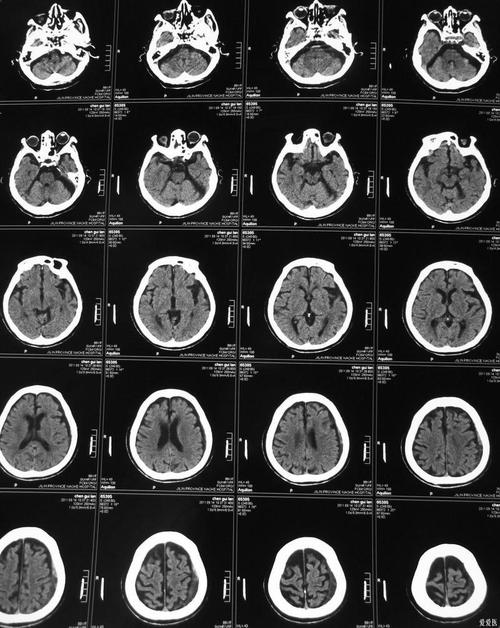

(图片来源网络,侵删)